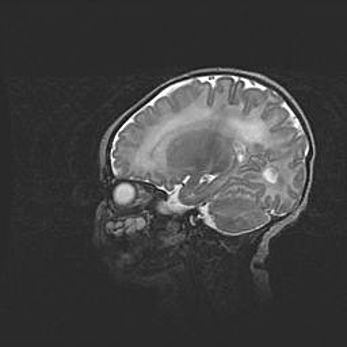

Мальформация Денди-Уокера. Киста задней черепной ямки.

Агенезия мозолистого тела.

Возраст: 2,5 месяца

Вес: 2420 г

Пол: женский

Окружность головы: 37 см

Срок гестации: 32 недели

Мальформация Денди—Уокера — редкий вид патологии ЦНС, представляющий собой врожденный порок развития каудального отдела ствола и червя мозжечка, ведущий к неполному раскрытию срединной (Мажанди) и латеральных (Лушка) апертур IV желудочка мозга. Для этогно синдрома характерна триада симптомов: гипотрофия червя мозжечка и/или полушарий мозжечка, кисты задней черепной ямки, гидроцефалия различной степени. В 70% случаев порок сочетается и с другими аномалиями головного мозга, в частности с агенезией мозолистого тела.